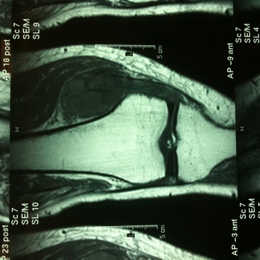

Radiographic imaging is used to help form a diagnosis. These include X-Ray, MRI, CT and Bone Scans

An example of an Synovial Sarcoma MRI is shown.